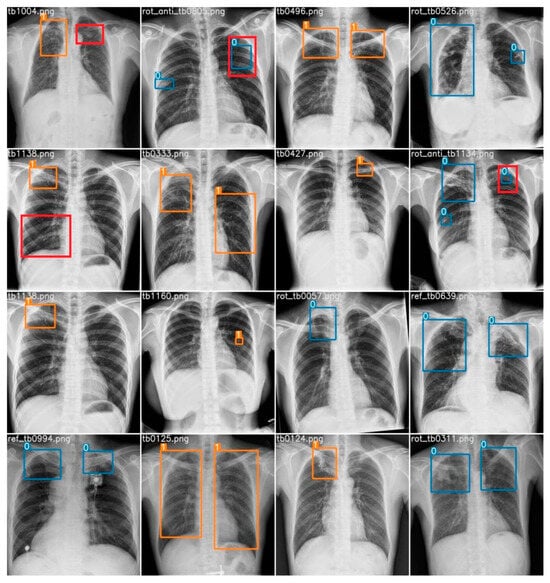

A random subset comprising 16 chest X-ray images was extracted from the dataset for analysis. Employing our computer vision model, various regions of imaging anomalies were detected within these images. To establish a benchmark, the predictions of the model were juxtaposed with interpretations provided by a radiologist, regarded as the reference standard. The radiologist identified a total of 25 abnormalities, consisting of 24 cases of airspace opacity, indicating a robust indication of TB infection, and 1 instance of cavitation. In terms of the model’s performance, there were 23 true positives, 2 false positives, and 2 false negatives. Specifically, the AI accurately identified 22 instances of airspace opacity and correctly flagged 1 case of cavitation. However, the model failed to detect two instances of airspace opacity and erroneously labeled two healthy lung regions as abnormalities. Figure 15 provides visual representations of the true positive, false positive, and false negative cases. Here, the orange box indicates an active TB infection, the blue box indicates an obsolete pulmonary TB infection, the red box indicates a false negative, and the red box outside the prediction box represents a false positive.

Figure 15. Prediction of all 16 random test samples with indication of false positives (red box outside prediction) and false negatives (red box). Here, blue box stands for obsolete cases and orange box stands for active cases.

Information 14 00655 g015

After incorporating genetic algorithms to optimize the hyperparameters in the YOLO model, our research findings indicate that the proposed CAD system achieved a promising mAP of 0.587, as illustrated in Figure 14. Our model outperforms previous formally recorded models, which are recorded in Table 1. Figure 16 also illustrated that the classification loss generalized well in the validation set with respectable numbers, concluding there was no overfitting of our model for the boundary box classification task. Also, the professional’s evaluation of our model in the randomly chosen test set depicts a decent result and practicality of our model, as shown in Figure 15. The developed CAD system holds great promise for the medical community, providing a more efficient and accurate approach to TB detection in chest X-rays. With seamless integration through a Django server and leveraging key deep-learning libraries like TensorFlow and PyTorch, our system can aid healthcare professionals in the early identification and diagnosis of TB, potentially leading to improved patient outcomes and reduced disease transmission through effective pattern recognition.

Importantly, we stress that our model should not replace the expertise of radiologists but serve as an assistive technology. The mAP of 0.587 on the validation set instills confidence in the model’s pattern recognition capabilities, making it a promising assistive tool for radiologists. The claim is further supported by the analysis of our model conducted by a professional radiologist, as presented in Figure 15. The example result of the model’s predictions on random samples on test set images suggests a fair applicability, strengthening confidence in its potential clinical utility in the context of the pattern recognition of TB infection.